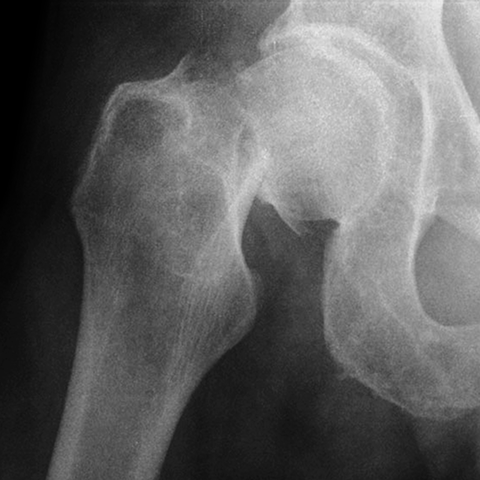

Fracture of Femoral Neck